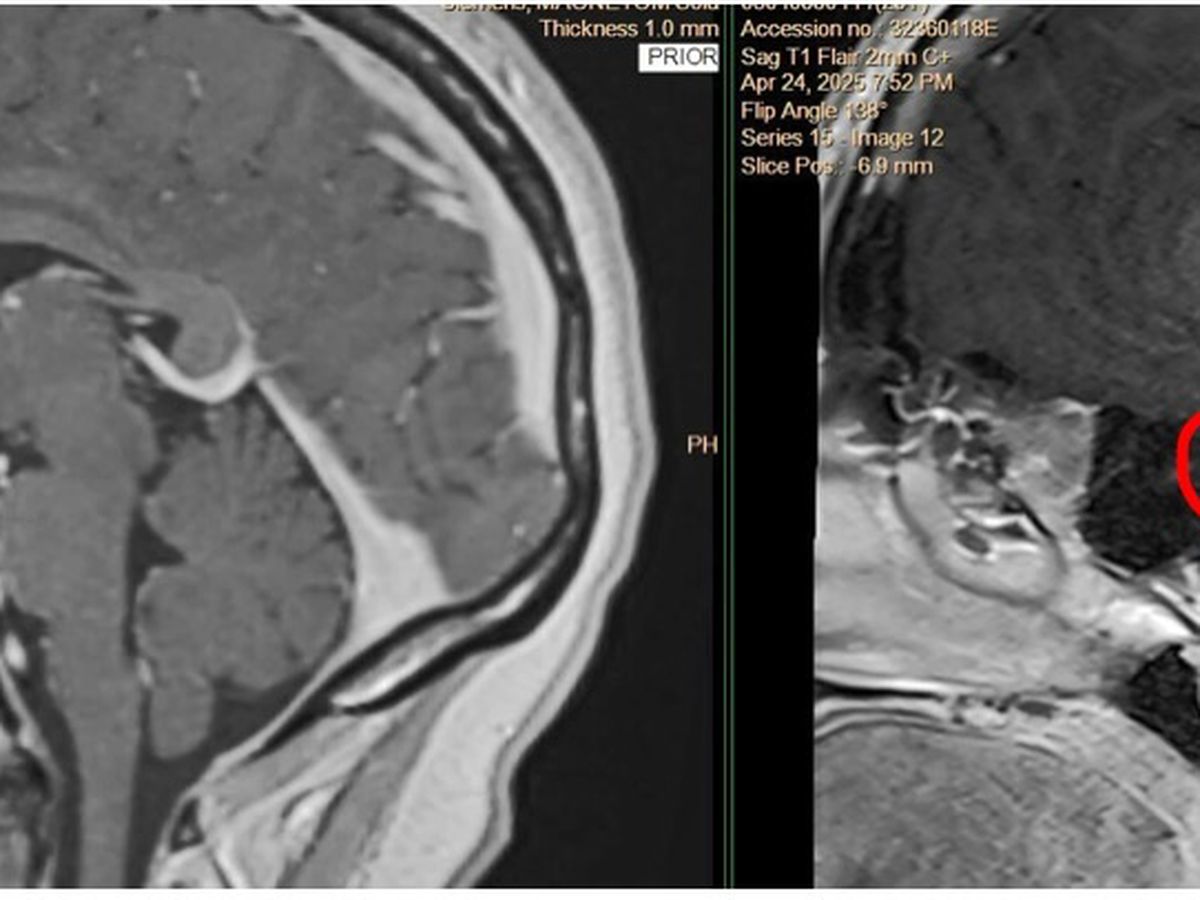

I was unexpectedly part of a mass layoff on May 19th, and shortly after, I received a life-changing diagnosis of scleroderma, a rare autoimmune condition. Now, I’m preparing to undergo brain surgery on July 17th at The James in Columbus.